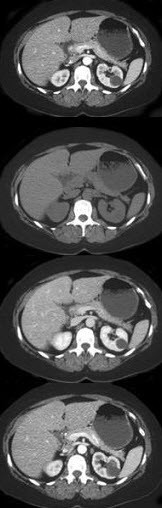

男,58岁,有高血压病史,突发胸背剧痛,CT扫描如图,其最可能的诊断为( )

A:主动脉瘤

B:主动脉假性动脉瘤

C:主动脉窦瘤破裂

D:高安病

E:主动脉夹层动脉瘤